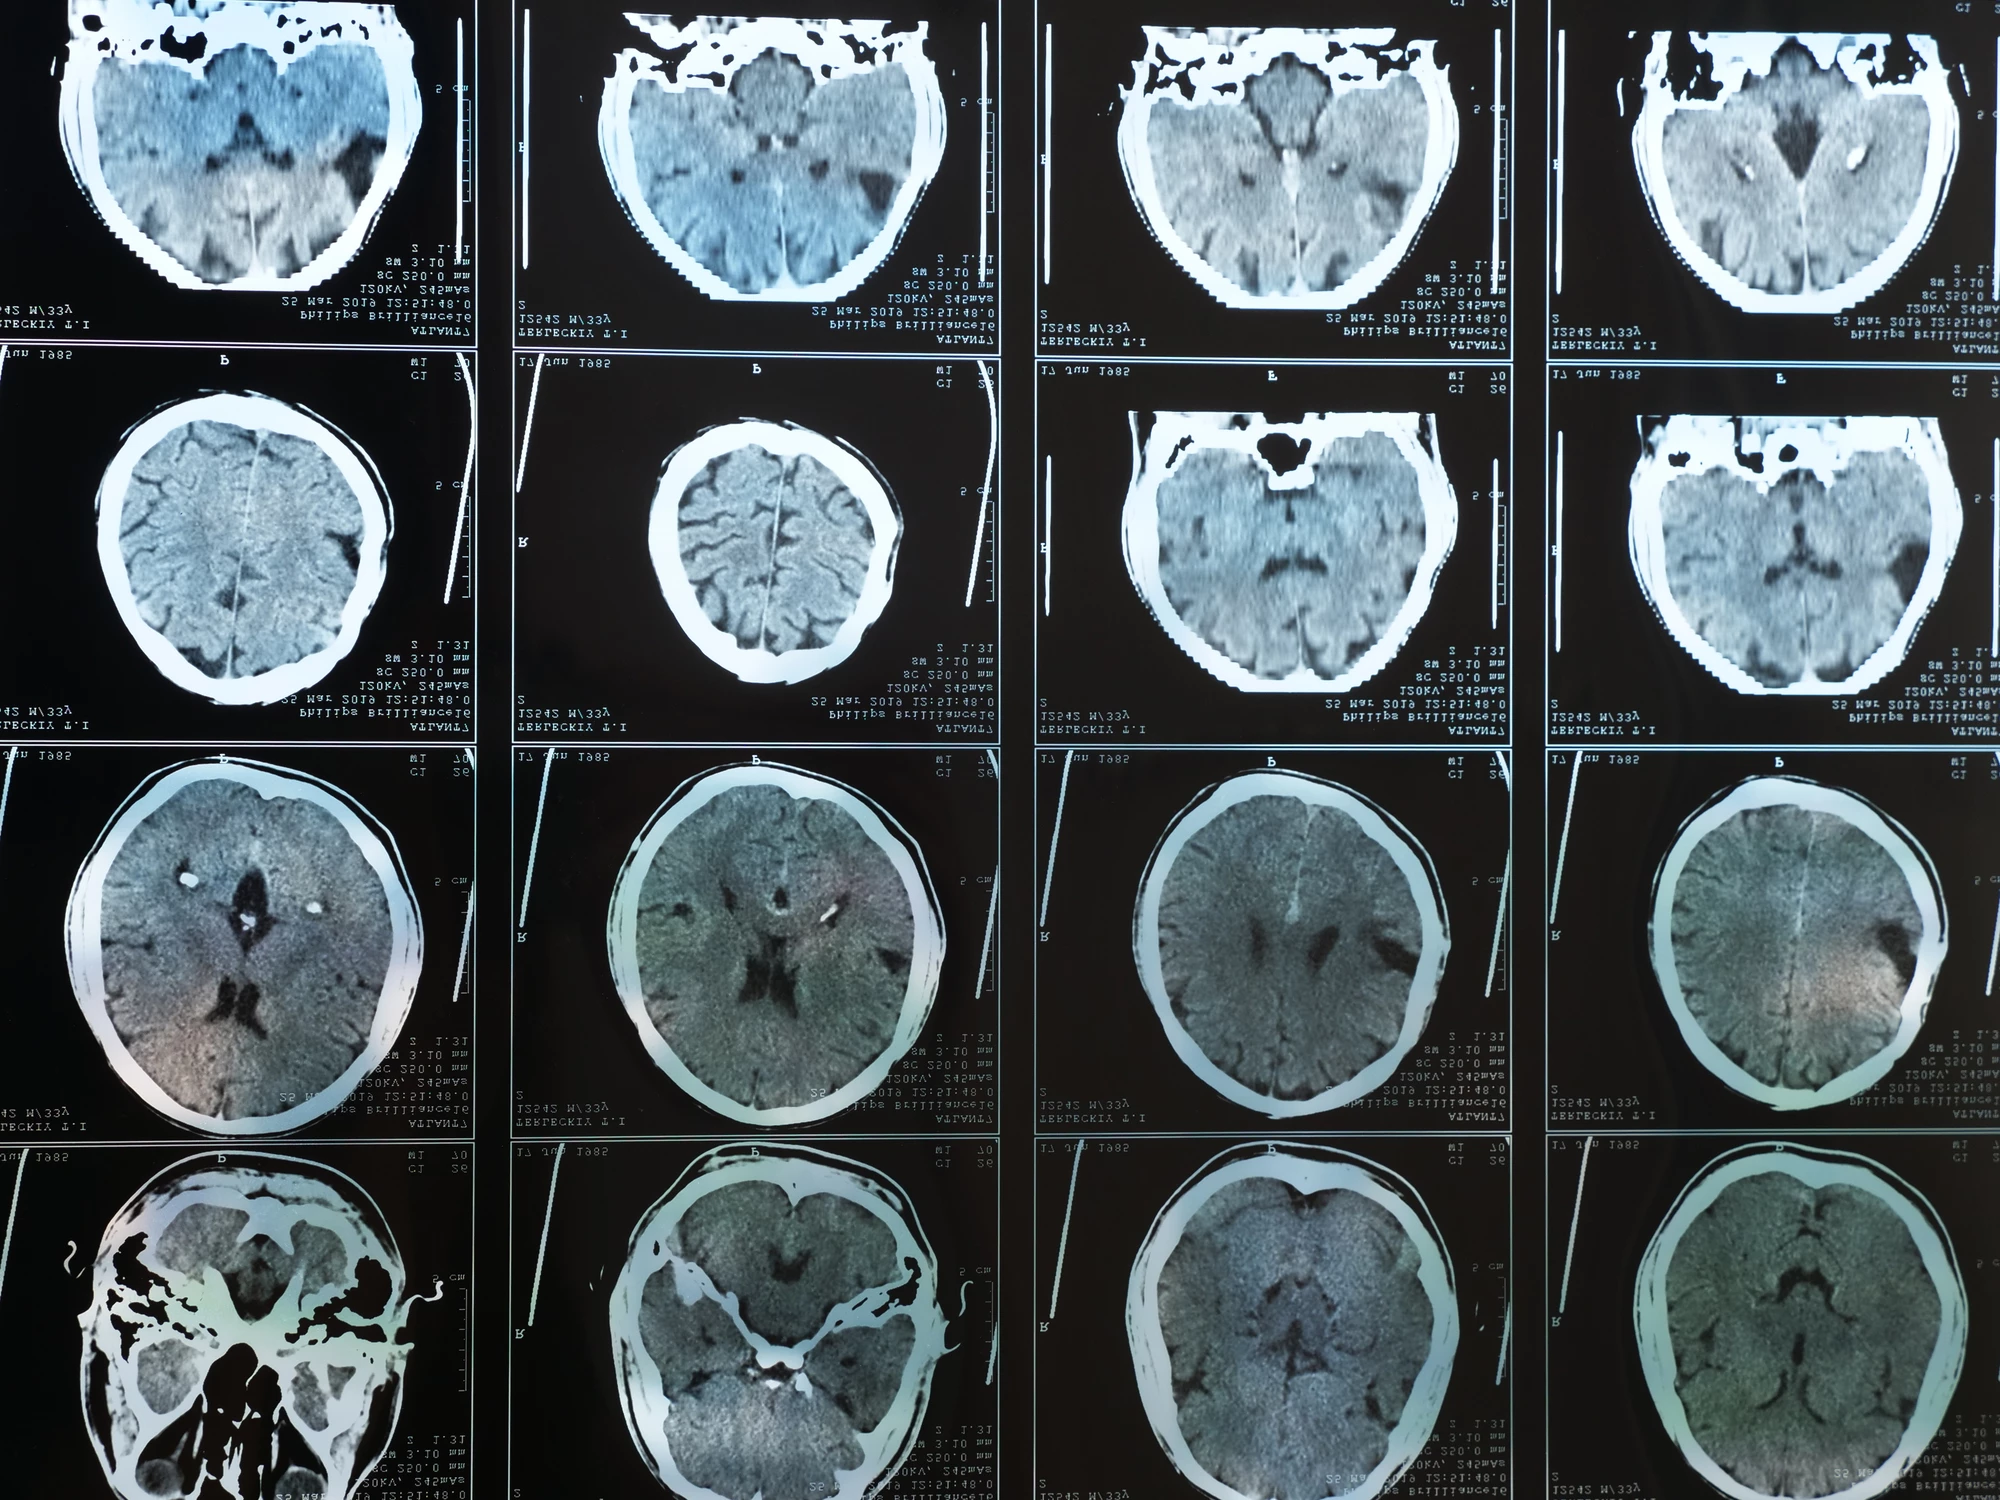

In a new study conducted by a team of US researchers, brain scans from more than 17,000 subjects were analyzed to investigate the association between body weight and cerebral blood flow. The patterns detected were striking, with blood flow across a number of brain regions decreasing relative to a greater body mass index.

The observed decreases in cerebral blood flow were particularly noted in five key brain regions relevant in subjects with Alzheimer’s disease – the temporal lobe, parietal lobe, hippocampus, posterior cingulate, and precuneus.